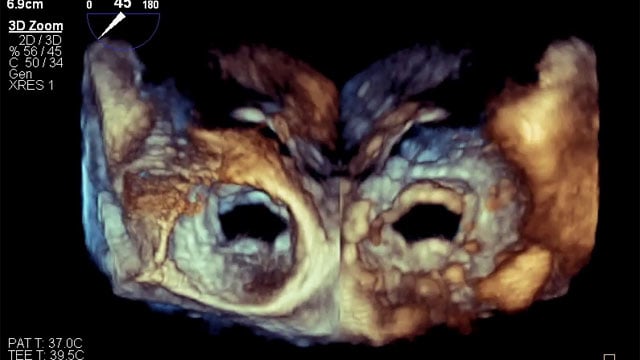

How should I manage a patient with insufficient surgical closure of the left atrial appendage

Incomplete surgical LAA closure: how would you proceed?

Despite prior closure with an Atriclip during CABG, transoesophageal echocardiography reveals a persistent LAA gap in a high-risk patient with recurrent bleeding.

Explore the clinical details, imaging, and treatment dilemmas—then share your management approach!